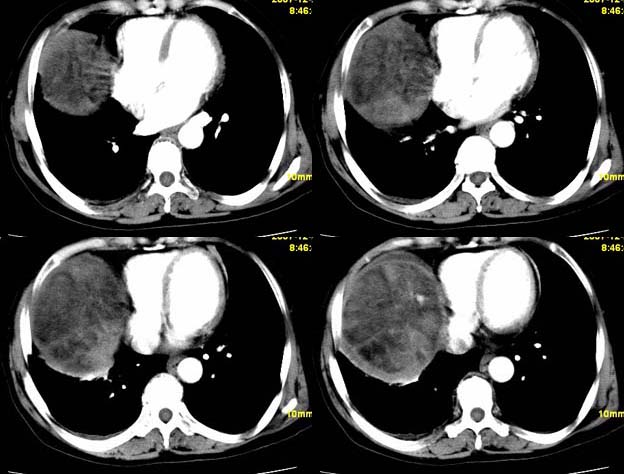

标题: CT11039:肝脏占位,平扫加增强,很“漂亮”的图像。

女,67,自诉右上腹痛10天,余病史未提供。

平扫低密度ct值约-14hu.